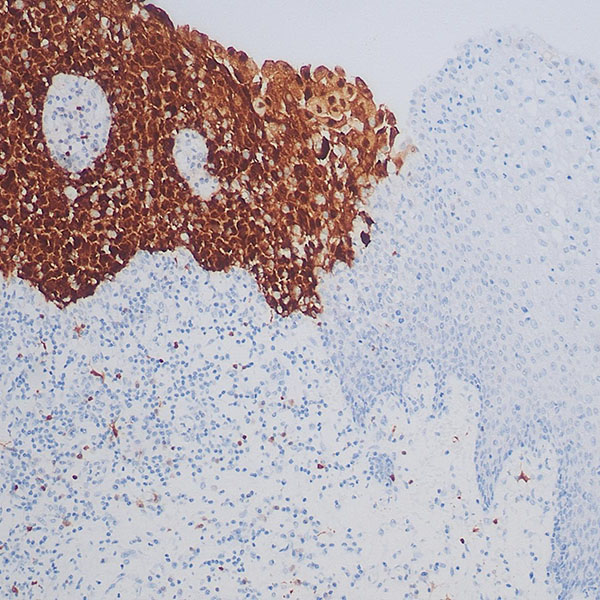

免疫组化染色